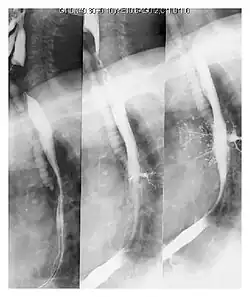

Aspiration seen on barium swallow study.

A fluoroscopic swallow study can be done in cases where dysphagia or motility disorders are thought to be the source of aspiration. Food and drink are mixed with barium contrast and monitored using x-ray to evaluate swallowing. Aspiration can be diagnosed if contrast is seen coursing below the vocal cords into the trachea.[13]